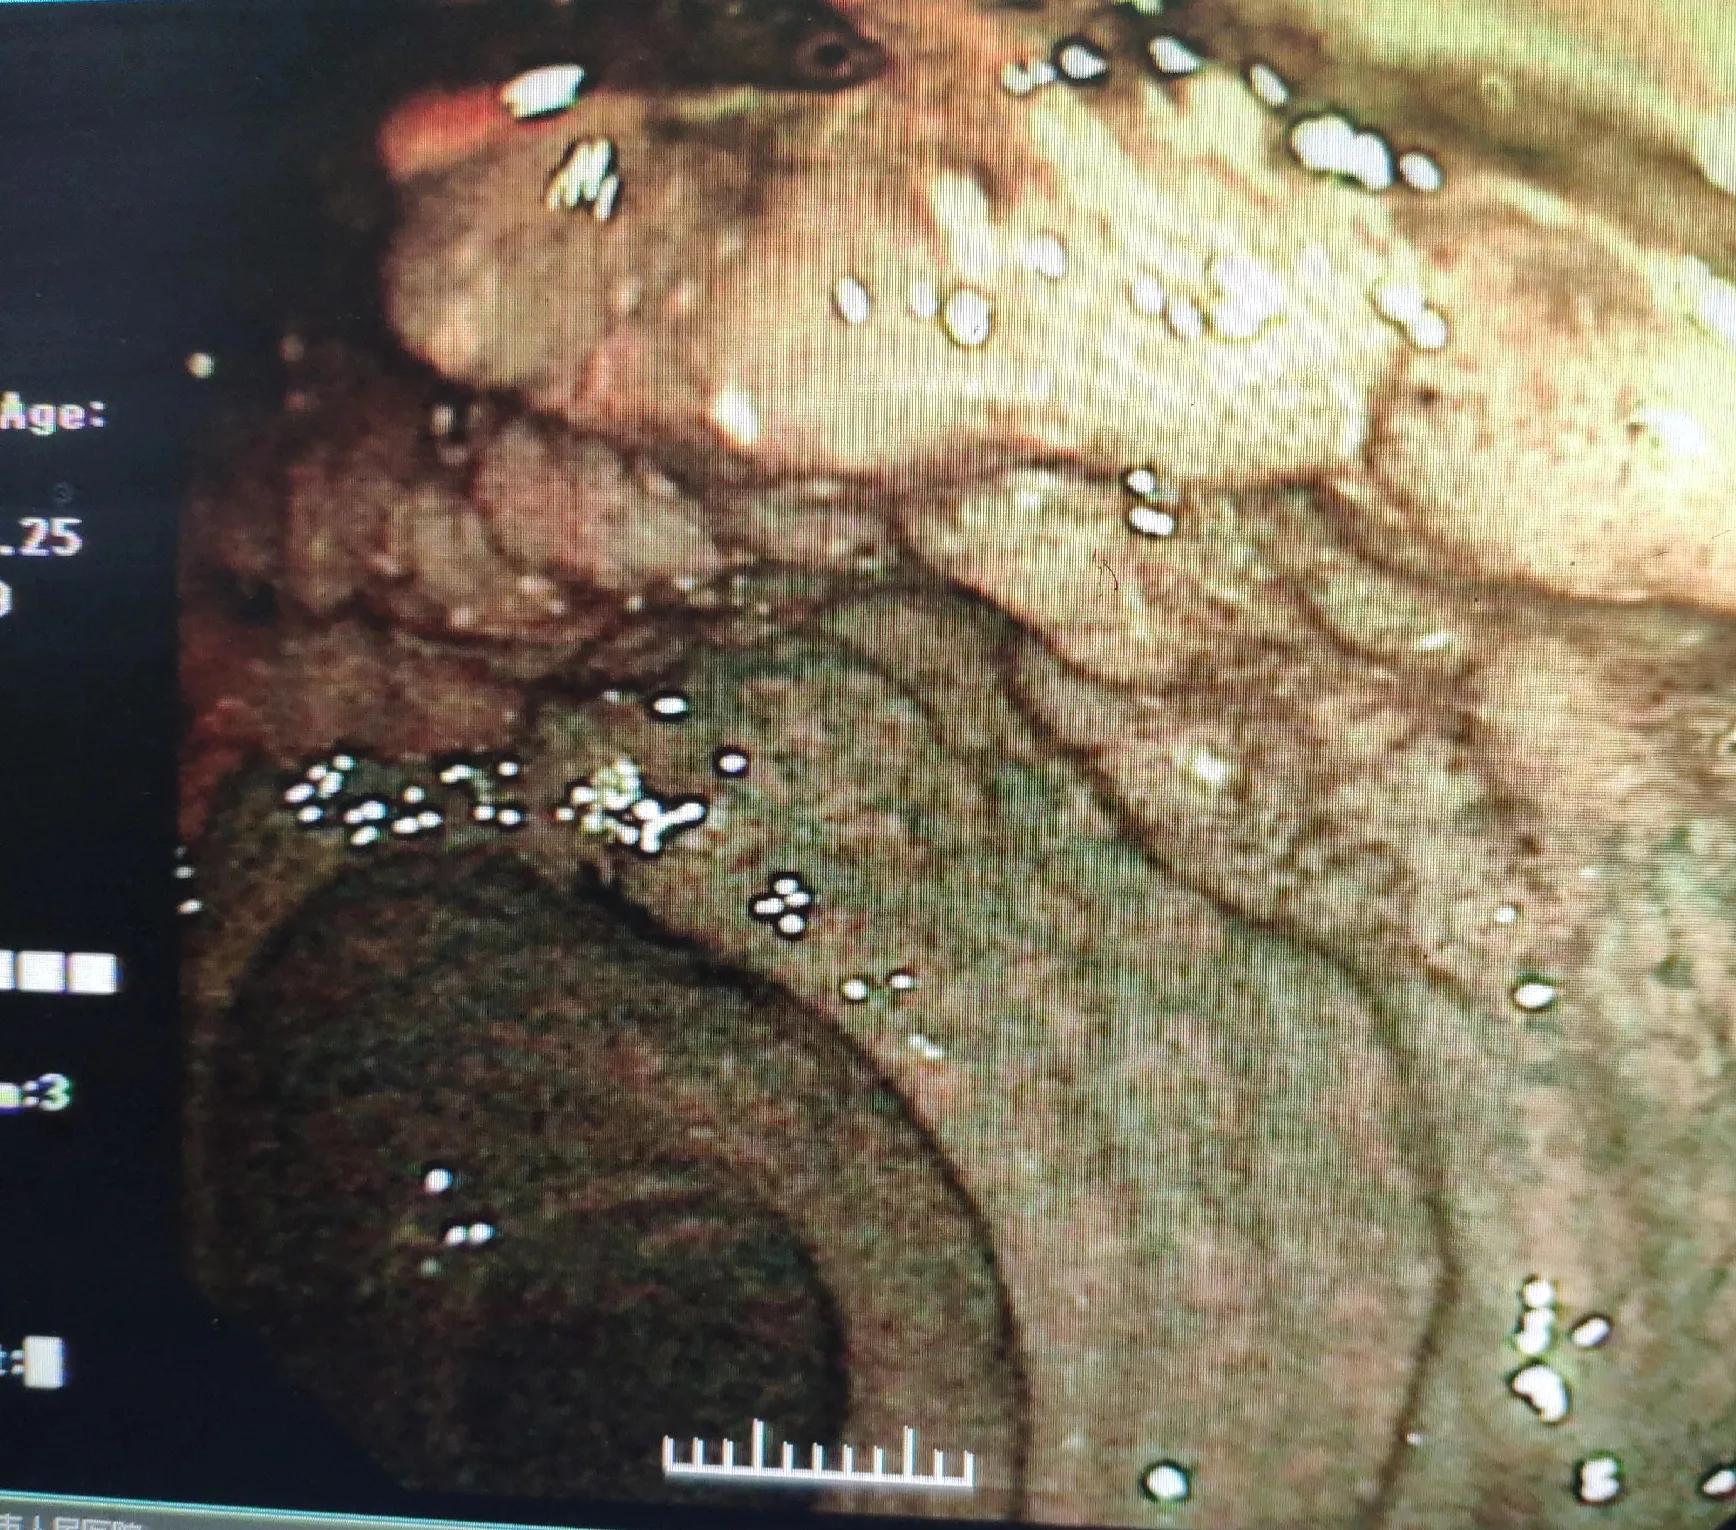

席大爷,今年67岁,一年前开始出现大便不规律,次数多,3-4次,稀烂状,时有里急后重,到医院消化科就诊,医生建议查了肠镜,发现多发性乙状结肠息肉,直径0.5cm左右,有3枚,给予了咬除活检,直肠距肛缘见长径范围达6cm的侧向发育性肿瘤,局部夹取了2块活检。直肠肿瘤见下图。

肠镜所见直肠病变,呈扁平隆起状

入院当日即进行了各项术前检查与肠道准备。第二天,在手术室进行了内镜下直肠病灶切除术:直肠可见7.5cm*6cm侧向发育性肿瘤,中央见大结节,予以黏膜下注射美兰+肾上腺素+甘油果糖抬举病灶,切开刀预切开病灶边缘,建立隧道,逐步完整大块剥离病灶,热钳处理创面,钛夹缩小创面。(术前术后镜下下图)

术前肠镜下病灶